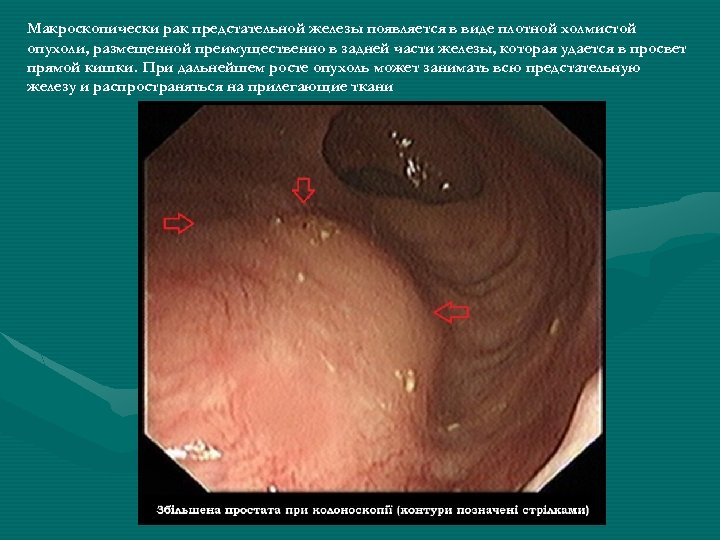

Макроскопически рак предстательной железы появляется в виде плотной холмистой опухоли, размещенной преимущественно в задней части железы, которая удается в просвет прямой кишки. При дальнейшем росте опухоль может занимать всю предстательную железу и распространяться на прилегающие ткани